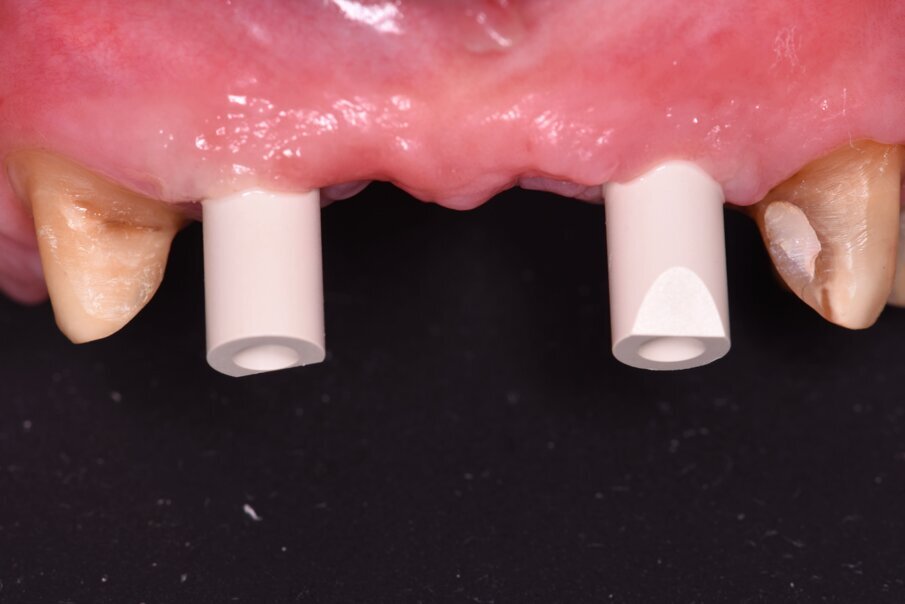

La rigenerazione ossea è stata ottenuta secondo l’impiego di biomateriale di origine bovina demineralizzato e stabilizzato con una membrana a lento riassorbimento in pericardio nativo fissata con dei chiodini in titanio (Fig. 23). Com’è noto la stabilità dell’innesto è un requisito indispensabile per ottenere una reale rigenerazione ossea stabile nel tempo. Dopo 4-6 mesi si effettua una radiografia di controllo eseguendo successivamente un opercolo perimplantare. In questo caso data la lieve deiscenza presente si è optato per l’impiego di un diatermocoagulatore per limitare il danno biologico ai tessuti limitrofi e mantenere inalterata la rivascolarizzazione della sede, inoltre non essendo un materiale metallico ma bensì ceramico, l’eventuale contatto viene disperso e non assorbito dall’impianto (Fig. 24). Data l’ottima stabilizzazione funzionale e volendo contenere i costi viene realizzata un’impronta digitale dell’arcata col primo provvisorio in situ e alla sua rimozione un’impronta dell’intera arcata con e senza gli scan body implantari (Fig. 25). Per mantenere l’opercolo ottenuto si utilizzano delle cappette di guarigione sempre in Zirconia che serviranno anche per stabilizzare i tessuti perimplantari (Fig. 26). In laboratorio, l’odontotecnico su nostra indicazione potrà elaborare i file ricevuti, valutando la possibilità di avvitare direttamente il manufatto, solo in caso di forte disparallelismo si opterà per la cementazione. Definita la procedura, verrà realizzato solo il provvisorio su impianti modificando il primo provvisorio che sarà riposizionato dopo il sezionamento dei quadranti (Figg. 27, 28). Dopo il posizionamento del nuovo provvisorio rileviamo una nuova impronta studio (Fig. 29) che analizziamo col software dedicato dello scanner digitale utilizzato.

Fig. 25_Dopo opercolarizzazione si provvede a rilevare l’impronta con appositi transfer che per le impronte digitali si chiamano scan body e si differenziano per il tipo di impianto e per il tipo di scanner intraorale utilizzato.

I dati raccolti sono molti ma la procedura digitale consente di sommarli e confrontarli senza limiti e indicando le possibili migliori e correzioni lungo il percorso. Dopo un breve periodo di condizionamento dei tessuti (Fig. 30) rileviamo l’impronta master per la finalizzazione ultima della riabilitazione protesica. L’impronta degli elementi naturali viene rilevata posizionando dei fili detrattori secondo la tecnica del doppio filo mentre per gli impianti verranno usati gli scan body dedicati (Fig. 31). Le potenzialità digitali consentiranno di avere una stabile lettura della posizione di centrica rilevandola prima della rimozione dei provvisori e sovrapponendola a provvisori rimossi (Fig. 32). In laboratorio l’odontotecnico realizza i modelli (Figg. 33, 34) sovrappone le immagini (Fig. 35) e raccoglie gli elaborati dei vari passaggi che porteranno alla finalizzazione del progetto digitale (Figg. 36, 37). Gli impianti in Zirconia non offrono molte soluzioni protesiche, è importante che il loro posizionamento tenga conto di quest’aspetto mettendo l’odontotecnico nelle condizioni più favorevoli (Fig. 38). Questa sistematica prevede l’uso di un moncone in titanio cementato nella struttura protesica che permette l’avvitamento all’interno dell’impianto. Nella connessione implantare è presente un’intercapedine dove alloggia il collarino in titanio del T-base totalmente inglobato all’interno della zirconia, evitando comunicazioni coi tessuti adiacenti. Va comunque considerato l’aspetto tecnico importante legato allo spessore della struttura in zirconia che deve avvolgere l’intero moncone in titanio. (Fig. 39, 40).